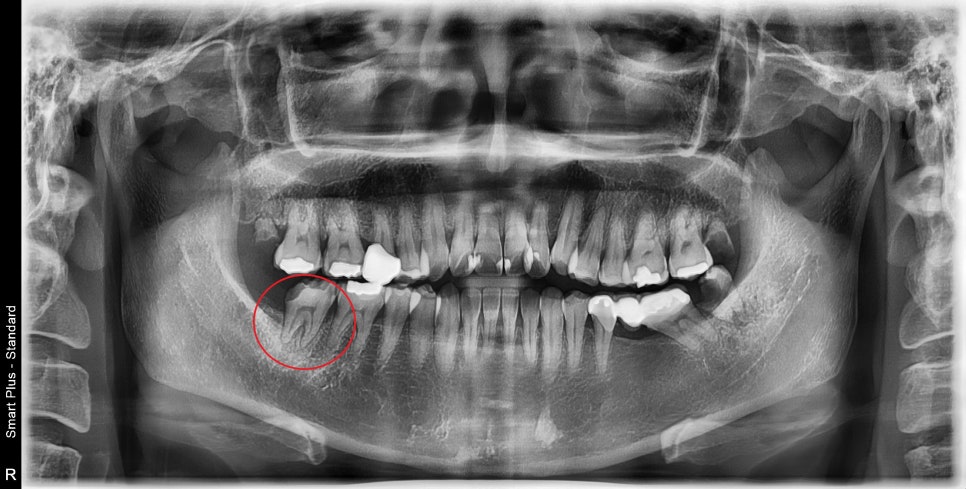

엑스레이에서 보듯이

최후방 치아가 깨지고 주변 치아뿌리인대가

비후 되어있었습니다.